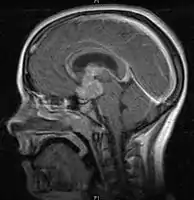

- Mainly located in midline structures, suprasellar region or pineal gland, also basal ganglia and hypothalamus

- Pineal Gland Germinoma

- Suprasellar Germinoma